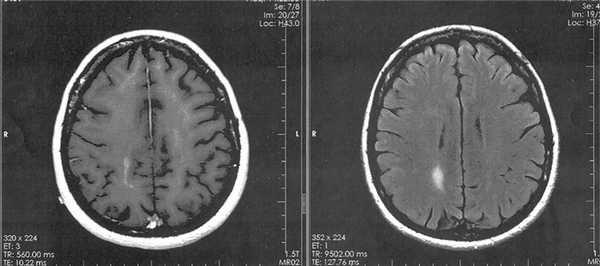

В процессе лечения подведено 20 фракций с РОД=1,8 Гр до СОД ср.=36,0 Гр. Облучение проводили 5 дней в неделю. На фоне лучевой терапии возникла офтальмогипертензия, которая была купирована инстилляциями Sol. Arutimoli 0,5%. В результате СРТ достигнута полная регрессия ПИОЛ (см. рис. 1, б), безрецидивный период составил 18 мес. Затем появились преципитаты на эндотелии роговицы, увеличилась инфильтрация стекловидного тела лимфомными клетками, что было расценено как локальный рецидив. Одновременно контрольная МРТ головного мозга выявила появление очага накопления контраста в правой теменной области - рецидив лимфомы полушарной локализации (рис. 3).

Рис. 3. МРТ головного мозга в аксиальной проекции: слева - в режиме Т1, справа - в режиме FLAIR, T2 (очаг накопления контраста в правой теменной области).

Контрольная МРТ головного мозга после облучения не выявила очага накопления контраста в правой теменной области или появления новых очагов лимфомы (рис. 5).

Рис. 5. МРТ головного мозга в аксиальной проекции через 3 мес после облучения на линейном ускорителе Primus.